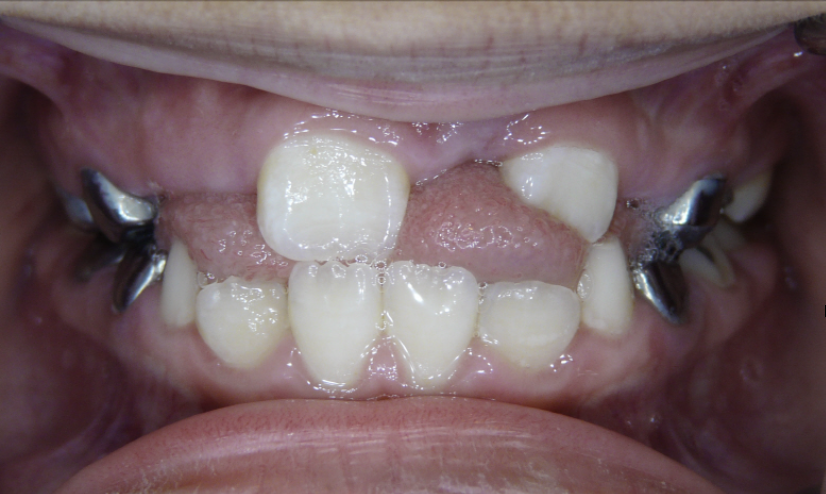

Ectopic Eruption

Ectopically erupting maxillary molar